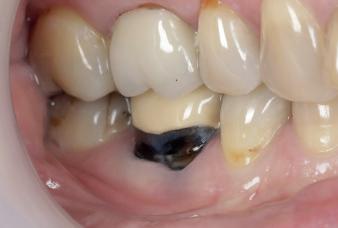

Case 1: Anterior tooth restoration with composite

Case 2: Posterior tooth restoration with composite

Restorations with Beautifil II LS, Beautifil Flow Plus X and OneGloss by Erik-Jan Muts, M.Sc., Netherlands